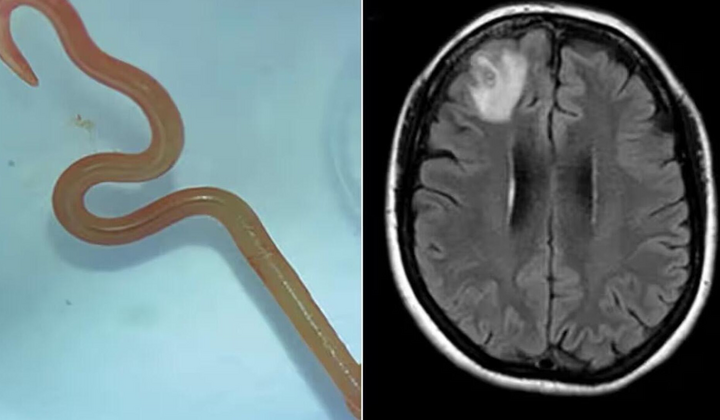

Там местная жительница обратилась к врачу с жалобами на головную боль. Кроме этого у нее были длинные моменты депрессии. После этого ей сделали МРТ, и результаты действительно всех удивили. Оказалось, что в мозгу женщины Ophidascaris robertsi, длиной 8 см. То есть червь. При этом он был жив.

После этого женщине сделали операцию и получили червя. Это первый случай в мире.